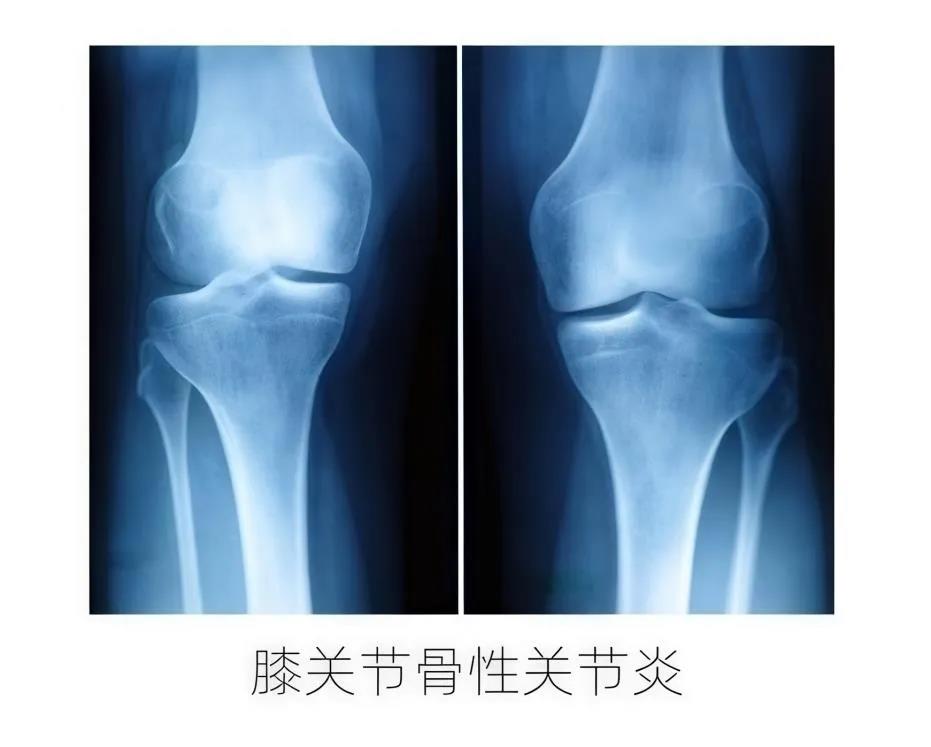

什么是膝关节骨性关节病?

骨关节炎是一种严重影响患者生活质量的关节退行性疾病,而膝关节骨性关节炎是发病率最高、临床最常见、损害最大的骨关节炎之一,主要表现为膝关节疼痛、肿胀和活动受限,若不及时干预和治疗,则会导致患者疼痛加重、关节破坏、膝关节严重畸形,最终需要关节置换。